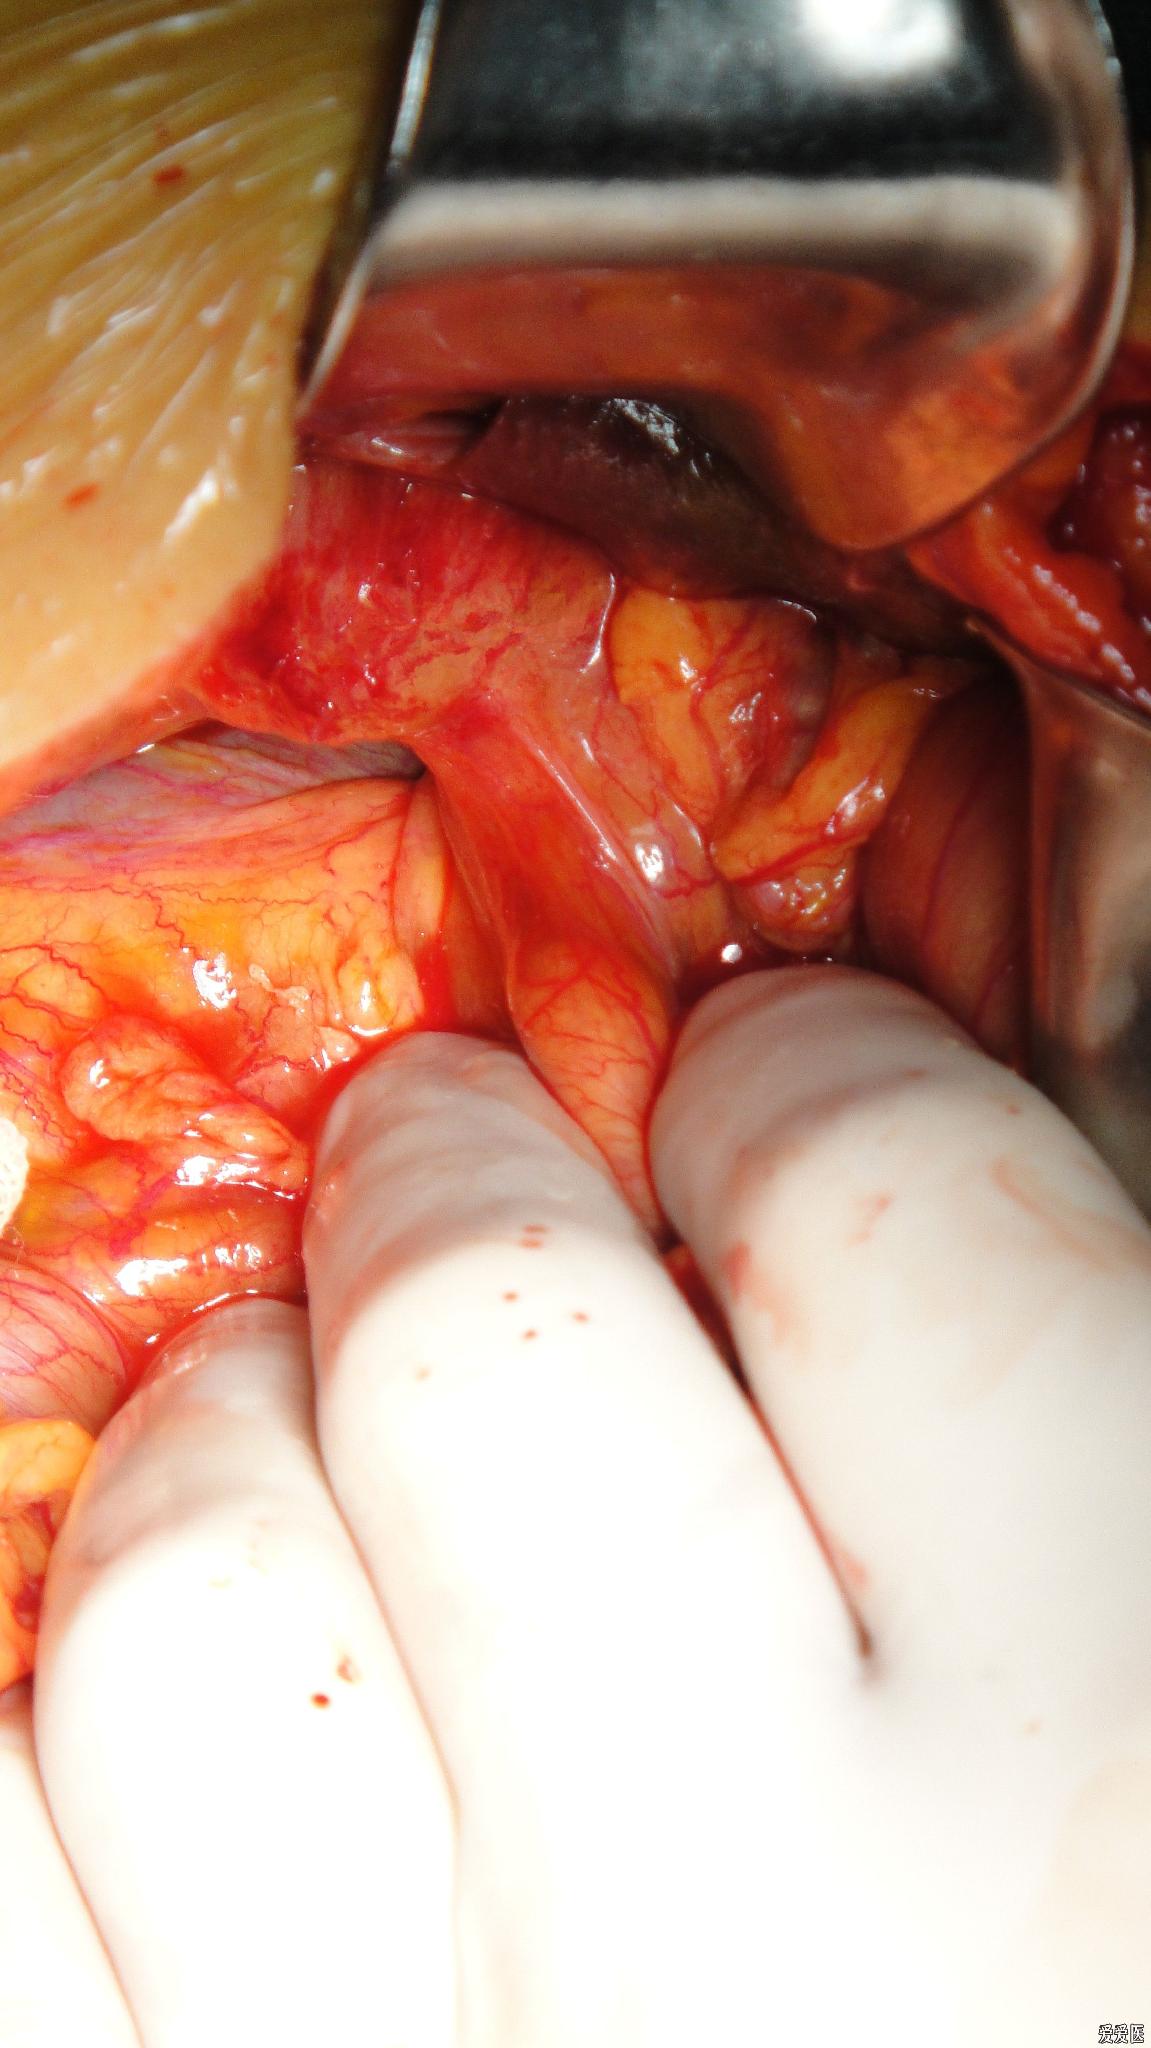

肝外膽管癌

肝外膽管癌初晚期

肝外膽管癌黃疸表現